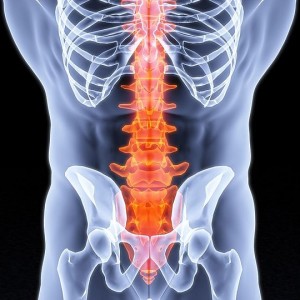

У многих больных наблюдается поражение костей именно в области позвоночника. Впрочем, иногда наблюдаются поражения и в костях черепа, а также таза. Симптомы болезни Педжета – сильная боль, деформация костей. Чаще всего, остеит возникает из-за переломов.

Обзор. Болезнь Педжета (PAJ-its) нарушает нормальный процесс регенерации костей в организме, при котором новая костная ткань постепенно заменяет старую. Со временем кости могут стать хрупкими и деформироваться. Чаще всего поражаются таз, череп, позвоночник и ноги.